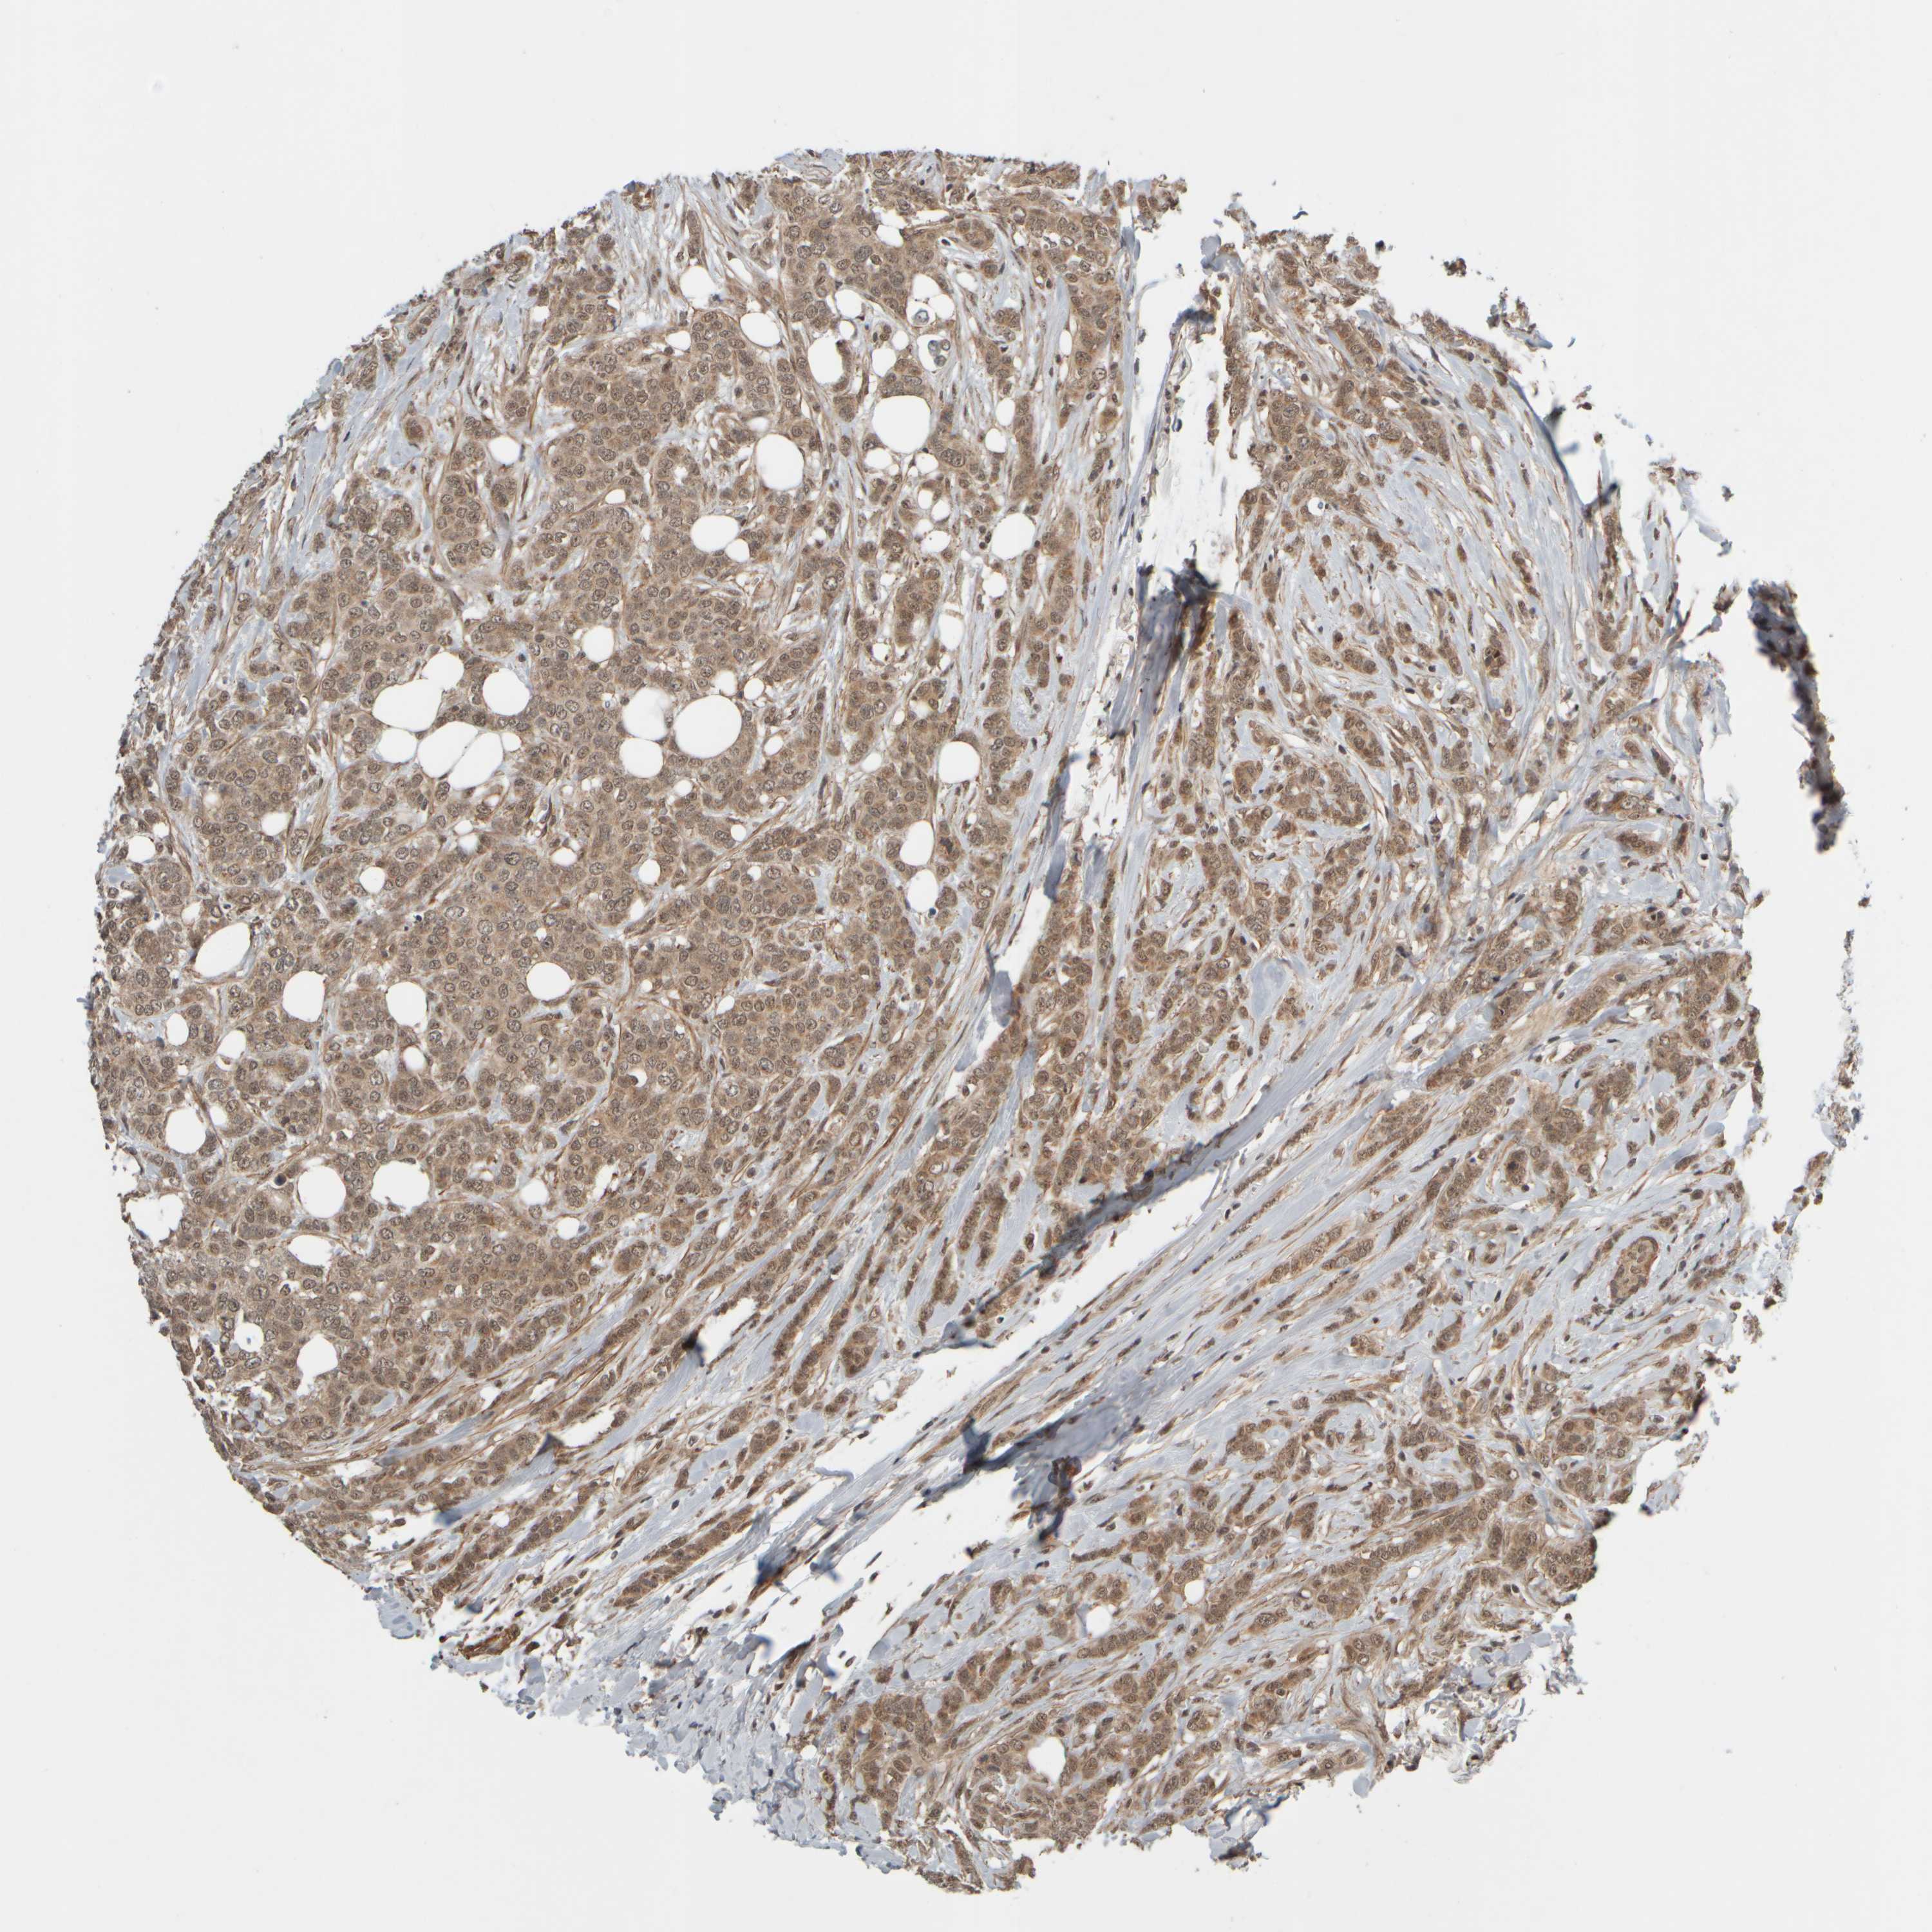

CANCER BREAST CANCER Show tissue menu

BRCA TCGA BRCA VALIDATION PROTEIN EXPRESSION